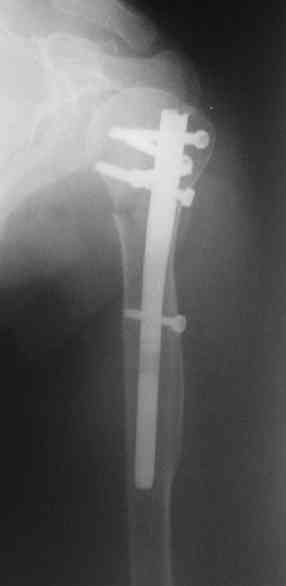

Another option could be closed nailing, see an example, the surgery was done 2 days ago. In common such surgeries are performed under regional anesthesia, not general.